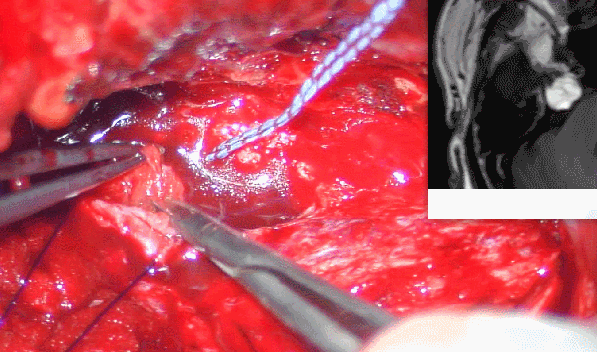

手术方案:1.解除右侧下颌神经骨性卡压;

2.肿瘤考虑为良性脂肪瘤,安全前提下尽力切除海绵窦-CPA区内占位;

3.肿瘤位于海绵窦内,卵圆孔-破裂孔区,为颅底孔道结构改变,采用前颞下经中颅窝入路,进入海绵窦区,术中避免损伤相关结构。